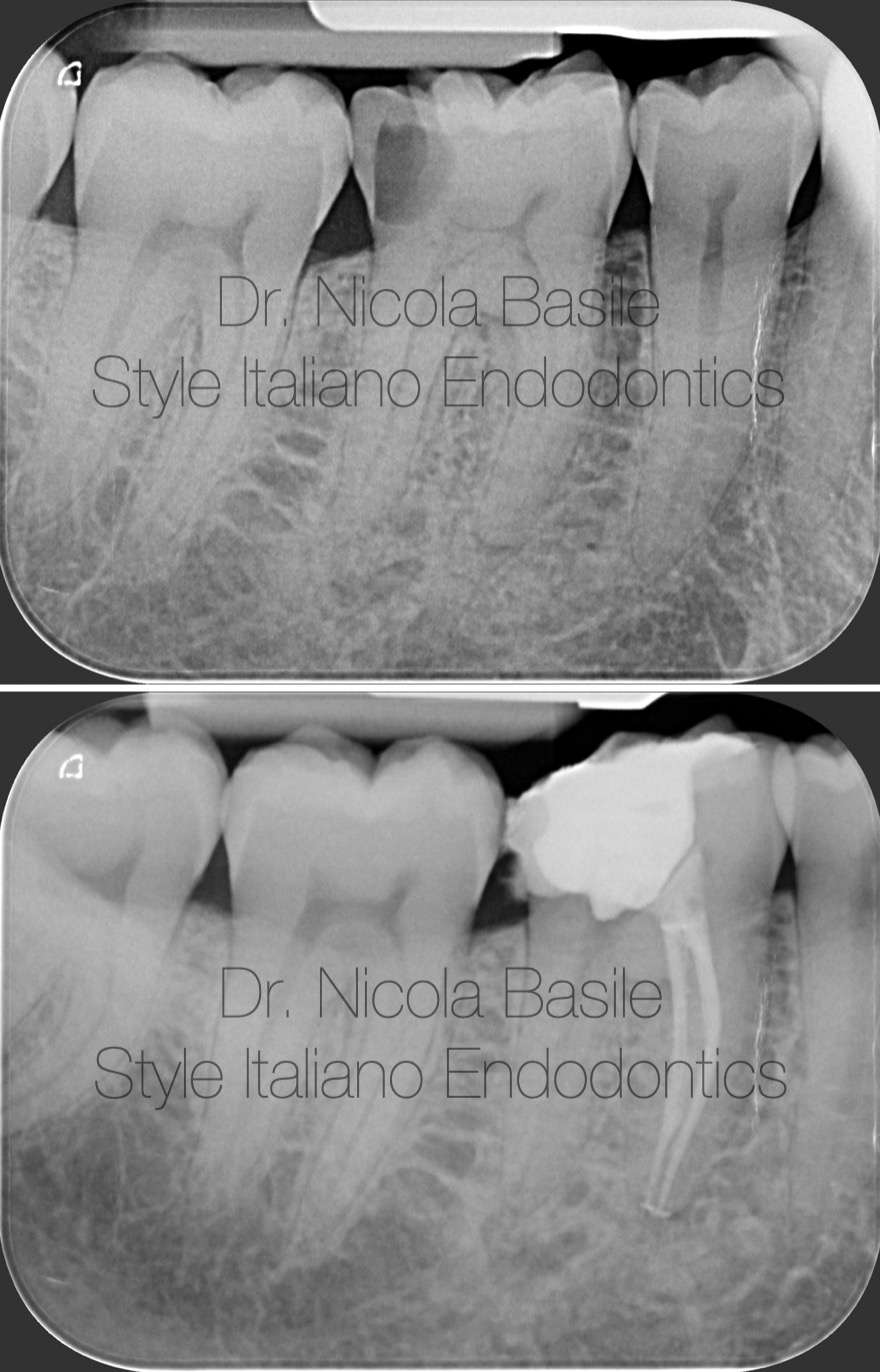

Fig. 5

Procedural phases of dental core build-up

Fig. 6

Tooth preparation for the fabrication of an onlay restoration.

Fig. 7

Optical impression using an intraoral scanner

Fig. 8

A monolithic milled composite onlay, designed and manually characterized by the technician

Fig. 9

Five days after surgery, an appointment was scheduled for the delivery of the onlay. Suture removal and isolation were performed.

Fig. 10

After trial fitting and verifying the accuracy of the onlay, the cementation procedure is carried out.

Fig. 11

Final finishing and polishing.

Fig. 12

The rubber dam was removed and the occlusion was checked.